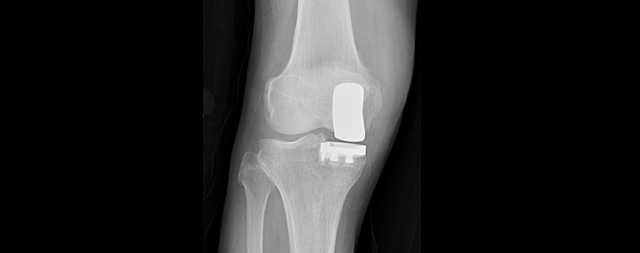

병변 심한 관절면만 부분적으로 제거한 뒤, 인공관절로 대체해 주변 인대나 힘줄, 근육 등 최대한 보존이 가능합니다.

전지환술에 비해 조직 이물감이 덜하고 수술 다음날부터 목발없이 걸을 수 있을 정도로 운동성이 우수합니다.

부분치환술은 추후 전치환술이 가능해 비교적 젊은 나이에도 수술을 받을 수 있습니다.

손상된 관절면 전체를 제거한 뒤, 관절구조와 가장 흡사한 규격의 인공관절을 만들어 새로 끼워넣는 방법입니다.

퇴행성 관절염 환자에게 적용하는 마지막 방법입니다. 통증없는 보행, 가벼운 등산, 수영 등 가벼운 운동이 가능합니다.